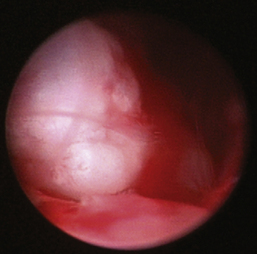

Nasopharyngeal Diseases

The hallmark symptom of nasopharyngeal disease is stertor. Discharge, sneezing, reverse sneezing, and hacking may be present variably. If the main complaint is noisy breathing and not productive sneezing with nasal discharge, the nasopharynx may be the site of primary disease. The most common primary problems in the nasopharynx in cats are inflammatory polyps and tumors.12,13 Cats with polyps are generally young and have a history of noisy breathing. Sneezing and mucopurulent nasal discharge may be present, but the chief complaint is stertor and increased respiratory effort. This is a problem that often requires otoscopic as well as rhinoscopic intervention. With the patient placed in dorsal recumbency, the soft palate is reflected rostrally with the use of a spay hook, and the polyp is removed via traction and avulsion (Figures 19-18 and 19-19). The eustachian tube orifices can generally be directly visualized and any remaining tissue removed, if present. Both ears should be carefully examined, and transtympanic bulla curettage should be performed to remove any middle ear proliferative tissue (see Chapter 20). In older cats with similar symptoms, a neoplasm in the nasopharynx is more likely, and rhinoscopy is often much more rewarding (Figure 19-20). Foreign bodies can become lodged in this area after vomiting or pharyngeal nasopharyngeal spasms induced by attempted swallowing of the foreign object. Nasal and nasopharyngeal stenosis after trauma, nasogastric reflux,14 and chronic rhinitis can occur in dogs and cats (Figures 19-21 through 19-23). Reflux can occur during general anesthesia and can be a helpful clue if postoperative symptoms arise and persist. Congenital choanal atresia and nasopharyngeal dysgenesis have also been reported in dogs.15,16 Nonspecific chronic inflammation of the nasopharynx causes a cobblestone appearance of the mucosa due to the formation of hyperplastic lymphoid follicles (Figures 19-24 and 19-25). Chronic inflammation may be the result of a lymphoplasmacytic rhinitis complex or sometimes may be secondary to otitis media and middle ear drainage of infected secretions via the eustachian tube. Otoscopy is recommended in any patient with nasopharyngitis of unknown origin. CT studies performed in a population of 45 cats with chronic sinonasal discharge revealed effusive bulla disease in 28% of symptomatic cats.17 Unfortunately, we are unable to differentiate primary and secondary pathology based on the concurrence of nasal and middle ear disease. Regardless of the knowledge of the primary cause, both inflammatory foci should be treated to achieve symptom relief.

image

Figure 19-18 Feline nasopharyngeal polyp visualization via soft palate retraction.

Figure 19-19 Feline benign nasopharyngeal polyp extraction.